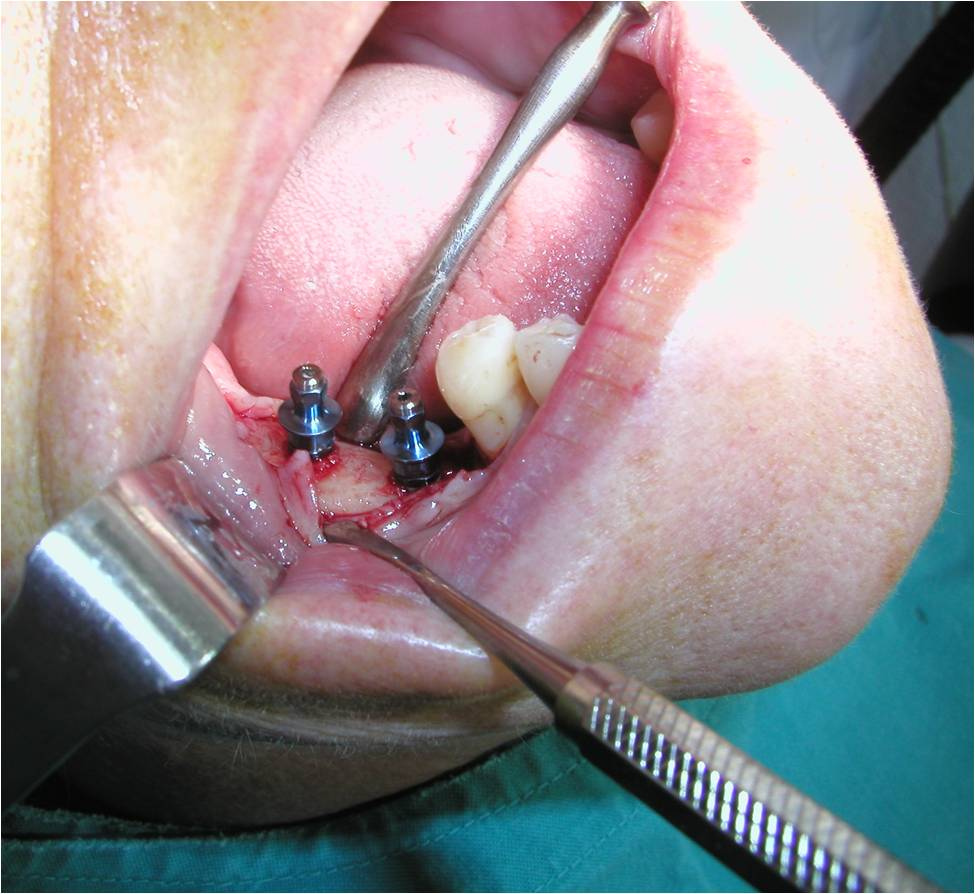

Colocación de implante meidante una de las técnicas que se darán a conocer en el III Curso de Regeneración y Reconstrucción Ósea en Cirugía Preprotésica Avanzada organizado por SECOM. Carlos Mateos/Rocío...